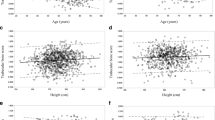

Statistical analysis

To be consistent with previous reports and because of the known differences in bone mineral and bone marker distribution, all analyses were performed separately for women and men. Mean ± SD and interquartile range, or percentages for categorical variables were used to summarize subject characteristics. Variables with non-Gaussian distribution were normal-scored transformed using Van der Waerden’s formula. The association between bone marker levels and QCT-derived bone measures was assessed visually using scatter plots, superimposing linear lines and also locally weighted scatter plot smooth (LOWESS) curves to examine potential non-linearity. Linearity was also examined with dummies by dividing bone marker levels into sex-specific quintiles (data not shown). Multivariable linear regression was used to determine the association between bone turnover markers and QCT parameters (as dependent variable). In the first stage of the hierarchical regression, we report the unadjusted model. We then adjusted for covariates including age, education level (low/high), age at menopause, history of osteoporosis or medication known to affect bone health (yes/no), and BMI (model 2). The third model added was adjusted for lifestyle factors including smoking status (yes/no), alcohol consumption (g/week), current physical activity level (low/high), mobility disability (yes/no), protein intake (g/day), coffee intake (yes/no), vitamin D intake (yes/no), and milk intake as a teenager (yes/no). History of diabetes (yes/no), CAC scoring, total 25OHD, PTH, and creatinine levels were added in the final model.

Results are expressed as standardized regression coefficient (β), p value, and the adjusted R 2 for both displayed models (unadjusted and adjusted/model 2). Results for model 3 and 4 were similar to model 2 (data not shown). Sensitivity analyses were conducted excluding BMI from the model to test the robustness of our results for the lifestyle variables.

Bone turnover markers and BMD (volumetric and areal)

All BMD measures, except for spine cortical BMD and P1NP in men, had a negative correlation with the BTM levels in both men and women (Tables 2 and 3). The association persisted after adjustment (models 2, 3, and 4), and there was no evidence of threshold effects when BTMs were categorized into quintiles (data not shown). In men, the correlation was stronger between femoral neck (FN) BMD measures and all BTMs compared to the same feature at the spine. The opposite was observed in women, although for spine cortical BMD slightly lower associations were observed, and it was only significantly associated with CTX and P1NP before adjustment for covariates (models 2, 3, and 4). Considering all bone measures, the highest simple correlation (unadjusted) was observed between each BTMs and integral BMD in both men and women. In both men and women, for all BTMs, the associations with the areal BMD were, in general, higher than those with cortical BMD, but lower compared with the other volumetric measures. The associations were stronger between BTMs and the trabecular bone than in cortical bone. Particularly in men, all models were very weak for FN cortical BMD; the final model only accounted for 1.4–2.0 % in its variability, while in women, the unadjusted model (each BTM) accounted for 1.0–2.2 %, and in the final model, only a modest improvement was observed (4.7–5.5 %). Thus, the cortical compartment displayed the lowest associations with BTMs. However, even for measures expressing trabecular bone, each BTM explained a small amount of the variation in BMD. For example, in men, serum concentrations of CTX, OC, and P1NP accounted for 9.0, 9.6, and 5.4 % of the variance in integral BMD, respectively, and in women for the same variable, the predictive values of each BTMs where less than half (CTX = 4.2 %, OC = 4.4 %, P1NP = 1.7 %).

Bone turnover markers and cross-sectional area

Associations of bone size parameters with BTMs levels were weaker and less consistent. In men (but not in women), all BTMs were positively associated with vertebral CSA. However, the magnitude of association of CTX and OC was extremely small (r = 0.10), thus accounting only for 0.8 % of the variance in vertebral CSA, and after adjustment, the final model only explained 4 % of the variance. Similar in men and women, CTX and OC did not correlate with FN minimal CSA. Small positive correlations (r = 0.09 in men and r = .07 in women) were found between P1NP and FN minimal CSA, and P1NP alone accounted for 0.7 % of the variance at this site in men and 0.4 % in women. All BTMs were associated with FN maximal CSA and the associations remained significant after adjustment (models 2 to 4). Each BTM accounted for 2 % of variance at the FN maximal CSA in men and accounted for less than 1.2 % in women. In men and women, adding age, BMI, education level, history of osteoporosis, or use of any medication known to affect bone health (and age at menopause for women) only slightly increased adjusted R 2 values at the trochanter to about 3 and 4 %, respectively.

Bone turnover markers and the integrity of the proximal femoral cortex

CTX, OC, and P1NP were inversely associated with FN cortical index in both men and women. The contribution of BTMs to the cortical index variance was lower in women compared with that in men (3.5, 3.2, and 1.0 % in women vs. 8.0, 9.0, and 4.5 % in men, for CTX, OC, and P1NP, respectively). Further adjustments had no influence on the results.

Bone turnover markers and bone strength

All BTMs levels were inversely correlated with vertebra compressive strength, being slightly higher in women compared with that in men. In men, P1NP was not significantly associated with vertebra compressive strength. CTX and OC remained significantly associated with vertebra compressive strength after adjustments. All BTMs were inversely associated with FN compressive strength, and the associations were stronger in men (medium magnitude) compared with those in women. All the associations persisted after further adjustments. In contrast to BMD measures, the associations between all BTMs and compressive strength in both men and women were stronger at the FN compared with those at the spine. Similarly, CTX and OC accounted for approximately 9 and 4 % of the variance in FN compressive strength, in men and women, with values for P1NP of 4.6 and 1.3 %, respectively. In addition, FN bending/torsional strength (section modulus) was not associated with P1NP in women, but a small inverse association (r = −0.09) was found in men. Bending/torsional strength was inversely associated with CTX and OC in men and women, and with P1NP only in men; however, in women, the association between CTX and FN section modulus was not significant after adjustments (models 2 to 4). The total variance of this strength index attributed to resorption and formation markers was lower for each BTMs. For example, CTX and OC accounted for about 3 % of variance in FN section modulus (less 6 % compared with FN compressive strength).